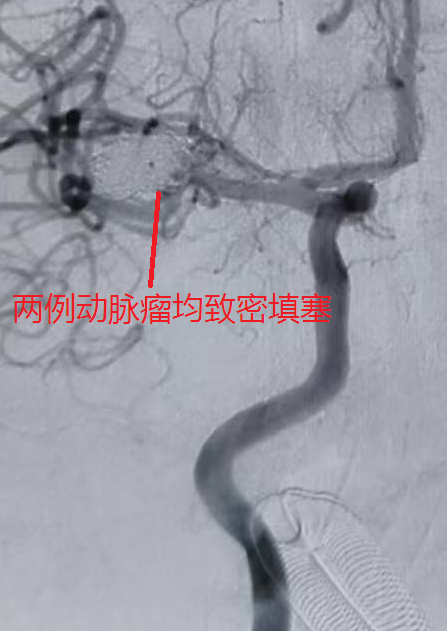

63 岁的女性患者,突发 “剧烈头痛 2 小时” 后被送往医院,颅脑 CT 同样提示蛛网膜下腔出血,CTA 检查高度怀疑右侧大脑中动脉动脉瘤。术中发现,患者右侧大脑中动脉M2分叉处存在两处瘤样凸起:一处为囊性凸起,约2.9mm×2.3mm,瘤颈2.1mm;另一处更大,呈椭圆形,大小约14.3mm×9.0mm,瘤颈6.5mm,瘤体右外侧见子瘤且累及下干,病情更为复杂凶险。

针对不同患者的动脉瘤特点,团队制定个性化手术方案:74岁患者的小脑后下动脉动脉瘤体积较小,手术历时 60 分钟顺利完成栓塞;63岁患者的双动脉瘤情况复杂,尤其是较大瘤体累及血管分支,手术难度更高,团队耗时100分钟成功实现两处动脉瘤的致密栓塞;43岁患者除动脉瘤栓塞外,因脑室内积血较多,术后紧急行 “脑室钻孔引流术” 释放血性脑脊液,降低脑积水风险,整个救治过程无缝衔接。